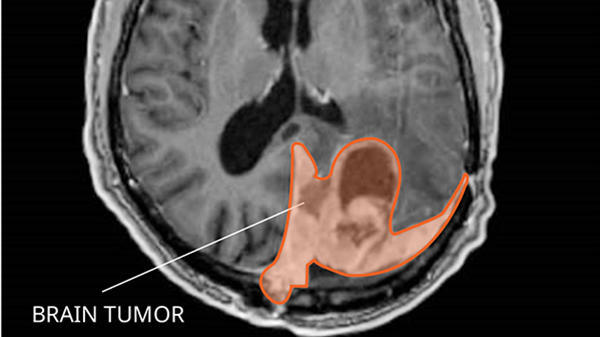

Brain and spinal cord (also known as central nervous system, or CNS) tumors can be benign or malignant. Explore the links on this page to learn more about the many different CNS tumor types and how they are treated. We also have information about brain cancer statistics, research, and clinical trials.